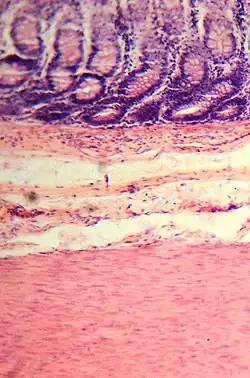

Colonic crypts

The wall of the large intestine is lined with simple columnar epithelium with invaginations. The invaginations are called the intestinal glands or colonic crypts.

The colon crypts are shaped like microscopic thick walled test tubes with a central hole down the length of the tube (the crypt lumen). Four tissue sections are shown here, two cut across the long axes of the crypts and two cut parallel to the long axes. In these images the cells have been stained by immunohistochemistry to show a brown-orange color if the cells produce a mitochondrial protein called cytochrome c oxidase subunit I (CCOI). The nuclei of the cells (located at the outer edges of the cells lining the walls of the crypts) are stained blue-gray with haematoxylin. As seen in panels C and D, crypts are about 75 to about 110 cells long. Baker et al.[30] found that the average crypt circumference is 23 cells. Thus, by the images shown here, there are an average of about 1,725 to 2,530 cells per colonic crypt. Nooteboom et al.[31] measuring the number of cells in a small number of crypts reported a range of 1,500 to 4,900 cells per colonic crypt. Cells are produced at the crypt base and migrate upward along the crypt axis before being shed into the colonic lumen days later.[30] There are 5 to 6 stem cells at the bases of the crypts.[30]

As estimated from the image in panel A, there are about 100 colonic crypts per square millimeter of the colonic epithelium.[32] Since the average length of the human colon is 160.5 cm[11] and the average inner circumference of the colon is 6.2 cm,[32] the inner surface epithelial area of the human colon has an average area of about 995 cm2, which includes 9,950,000 (close to 10 million) crypts.

In the four tissue sections shown here, many of the intestinal glands have cells with a mitochondrial DNA mutation in the CCOI gene and appear mostly white, with their main color being the blue-gray staining of the nuclei. As seen in panel B, a portion of the stem cells of three crypts appear to have a mutation in CCOI, so that 40% to 50% of the cells arising from those stem cells form a white segment in the cross cut area.

Overall, the percent of crypts deficient for CCOI is less than 1% before age 40, but then increases linearly with age.[29] Colonic crypts deficient for CCOI in women reaches, on average, 18% in women and 23% in men by 80–84 years of age.[29]

Crypts of the colon can reproduce by fission, as seen in panel C, where a crypt is fissioning to form two crypts, and in panel B where at least one crypt appears to be fissioning. Most crypts deficient in CCOI are in clusters of crypts (clones of crypts) with two or more CCOI-deficient crypts adjacent to each other (see panel D).[29]